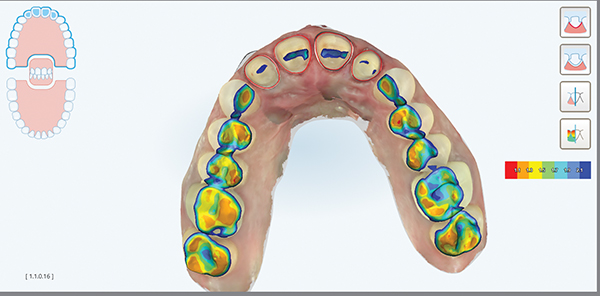

Fig 6. Scan of preparations with iTero Occlusogram activated. This feature shows occlusal clearance and occlusal contacts using a gradient feature and graphic key. This allows a clinician to quickly know if enough clearance has been achieved for fabrication of restorations.

Figure 6

Digital impressions are an effective alternative to conventional impression techniques and may be considered as the first option for impression-taking because of predictable, efficient, and simplified processes for both patients and clinicians.18 Using an intraoral scanner, such as the iTero Element 2 used in this case, affords the clinician many efficiencies that cannot be achieved with traditional polyvinyl siloxane (PVS) impression materials. Preparations can be reviewed and verified, including marginal clarity and restorative clearance, while the patient is still in the office. With a digital platform such as MyiTero (Align Technology, Inc.) or other comparable software, clinicians can quickly assess the quality of their preparations, marginal design, marginal visualization, and clearance between arches, as shown in Figure 11 and Figure 12, which are additional digital images of the preparations in this case. If any areas require modification, the clinician can complete those steps and rescan the areas as needed without having to reappoint the patient. Digital impressions also provide a permanent record storage of the case which can be revisited at any time.